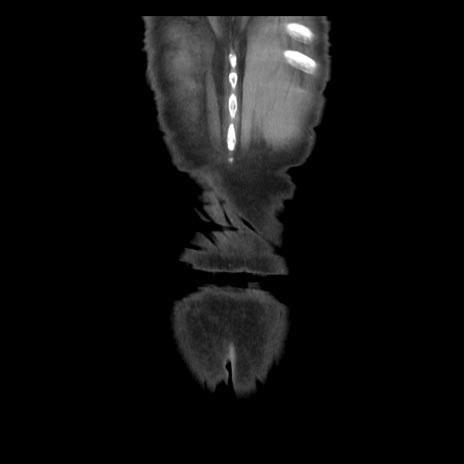

横断像